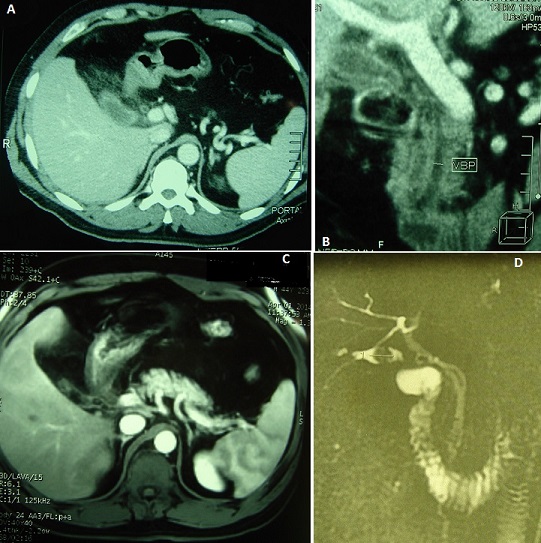

Une cholécystectomie subtotale expose au risque de cholécystite sur moignon, bien qu'elle constitue une option sûre face à une inflammation sévère du triangle de Calot permettant de réduire le risque de plaie biliaire. Malgré une histoire parfois typique, le diagnostic est souvent retardé en raison d'une faible suspicion. Par conséquent les cliniciens devraient évoquer ce diagnostic. Une fois le diagnostic confirmé, il convient de réaliser une ré-intervention pour exciser le moignon. Nous rapportons le cas d'un patient agé de 43 ans opéré par laparotomie sous-costale droite pour un pyo-cholécyste lithiasique. Il a été réalisé une cholécystectomie. L'examen anatomo-pathologique avait conclu à une cholécystite aiguë avec péri-cholécystite. Deux ans après, le patient présentait un syndrome douloureux et fébrile de l'hypocondre droit depuis trois jours et a été traité à tort pour pneumopathie droite avec une radiographie thoracique normale. A l'examen, le patient était fébrile à 38,5°c, et il existait une défense à la palpation de l'hypocondre droit. Il existait un syndrome inflammatoire biologique. L'échographie était non contributive. La tomodensitométrie avait montré un aspect d'une cholécystite sur moignon avec une infiltration importante tout autour. La cholangio-IRM avait montré une néo-cavité au niveau du lit vésiculaire d'environ 3,5x1,5 cm contenant une concrétion lithiasique ovalaire de 15 mm de grand axe qui se continue avec le canal cystique sans dilatation des voies biliaires. Sous couverture antibiotique, la reprise de la sous-costale avait permis, difficilement, l'exérèse du moignon et une cholangiographie per-opératoire montrant une vacuité des voies biliaires. Les suites opératoires étaient simples.